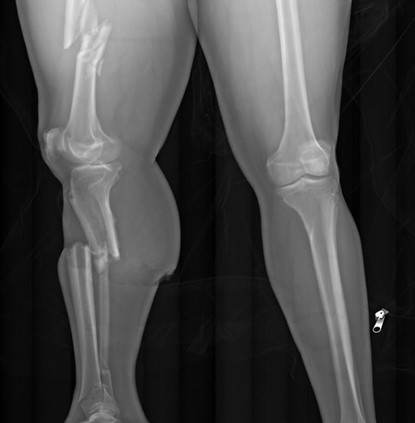

In the first pathway, consider an autopsy of a person with a single gunshot wound to the head. In a readily accessible region like the temple or beneath the chin, this wound could easily be self-inflicted. While this would be a “typical” location for a suicidal injury, such a wound could also be inflicted by another person. There are indicators we look for at autopsy which favor one scenario over the other. For example, most suicidal gunshot wounds (broadly speaking, of course) are contact wounds or intra-oral. A self-inflicted gunshot wound to the back of the head would be unusual, but (contrary to popular conception), not impossible depending on the firearm used. However, the same type of pattern could be elicited with another person holding a firearm to that individual’s head. We may examine the length of the firearm to determine if it’s possible for the decedent to have pulled the trigger themselves (keeping in mind that other items like a cane, coat hanger, or even the decedent’s toe, may have been used to depress the trigger). Similar questions can arise in autopsies of people who have fallen from height. There is no way an autopsy can tell with certainty whether an individual was pushed, fell accidentally, or left the edge of an elevated structure intentionally. The cause of death in both situations is undisputed – a gunshot wound in the first, and blunt force injuries in the second. This is why contextual information, like scene photographs and investigative records, is indispensable for forensic pathologists. Without context, we have no way to discern homicides, suicides, and accidents. Occasionally even with context, there can be competing narratives (one witness claims a gunshot wound was self-inflicted, while another claims it was inflicted by the first) or suspicious circumstances to cast doubt. Without clear cut evidence to support one story, the manner of undetermined is appropriate.

The second pathway by which we reach an undetermined manner is when extensive decomposition or other soft tissue loss (such as fire damage) interferes with our ability to determine a cause of death. Think of completely skeletal remains discovered in an abandoned building. Sometimes, indicators of potentially lethal injuries can still be identified – for example, a gunshot wound of the skull or knife marks on a rib. But, as the aphorism goes, “an absence of evidence isn’t necessarily evidence of absence” – a bullet or blade could be lethal while only striking soft tissue (especially in regions like the abdomen or neck). If we cannot rule out non-natural causes of death, the best choice for manner is “undetermined.”